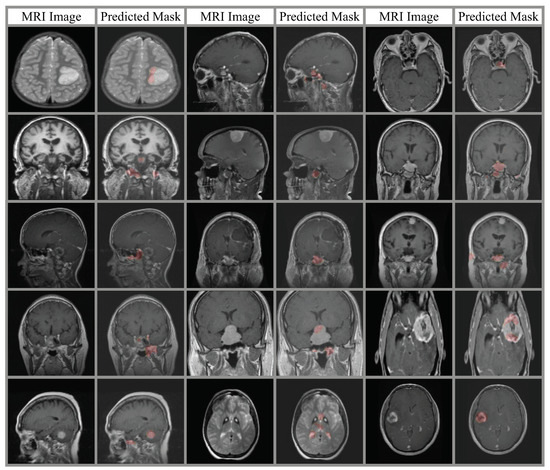

4. Experimental Results

4.2. Classification Results